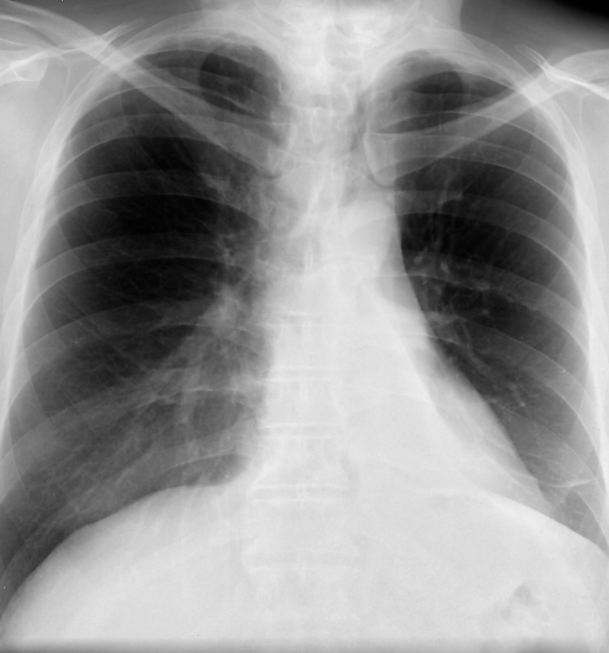

右中葉の無気肺の胸部単純X線写真

胸部正面写真で右心下縁(右第2弓)のシルエットが消失し、淡い陰影を認める(右第2弓でシルエットサイン陽性)。